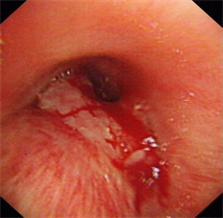

图片4 硅酮支架帮助重建气道

近日我科为一食道癌晚期、食道气道瘘的患者成功放置硅酮支架,患者在禁食1月后终于再次尝到了香甜的米饭,激动万分。该患者1年前在外院确诊为食道癌晚期,一直在我院放化疗科进行化疗及放疗,后患者逐渐出现进食后呛咳,复查胸部CT提示食道癌气道广泛侵袭,存在气道食道瘘可能。患者为避免进食后呛咳,已留置鼻饲,禁食1月。经我科俞万钧副院长会诊,决定为患者进行气道硅酮支架置入堵瘘口,让患者恢复进食。硅酮支架堵瘘术目前国际上开展不多,国内更是寥寥无几,手术难度大,成功率低。手术当日,俞万钧副院长亲自主刀,首先对气道浸润的肿瘤进行消融处理,后成功放置Y型硅酮支架,封堵瘘口。术后次日,患者就能进食流质,再次体会到进食的快乐。利用Y型气道硅酮支架封堵瘘口,全省目前未见报道,全国只有天坛医院,厦门二院等几家医院实施过,这一手术标志着我院硬镜,硅酮支架放置技术达到全国领先水平。(徐涛)